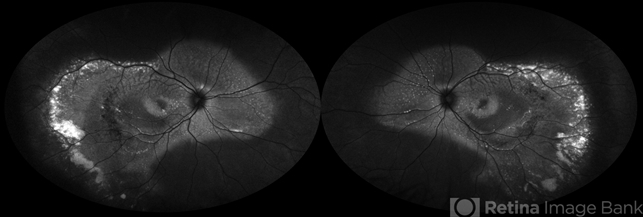

- Autosomal Recessive Best Disease

- Best disease, Autosomal recessive bestrophinopathy

- Fundus autofluorescence imaging of a patient with autosomal recessive Best disease